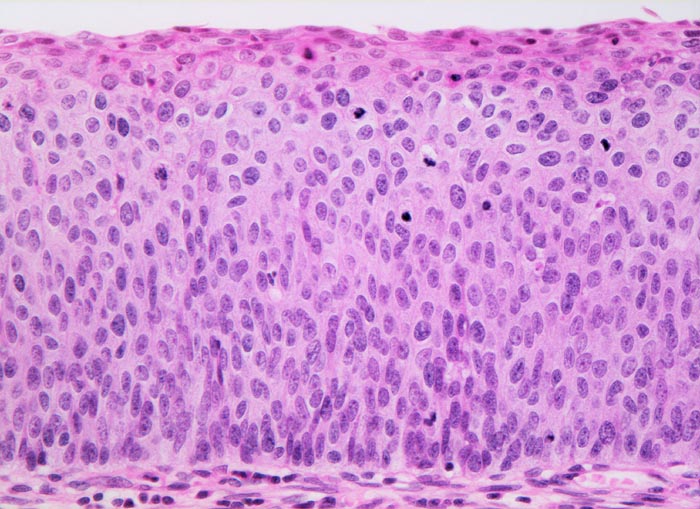

PathoPic – image database / PathoPic ID 4491 - Carcinoma in situ (CIN III) des Plattenepithels

Carcinoma in situ (CIN III) des Plattenepithels

Plattenepithel mit fehlender Ausreifung (wenig Zytoplasma, grosse Kerne) der dichtstehenden Zellen in der gesamten Epithelbreite. Mitosen lassen sich in diesem schwer dysplastischen Epithel bis in das obere Epitheldrittel nachweisen. An der Epitheloberfläche finden sich einzelne parakeratotische Zellen mit kleinen kondensierten pyknotischen Kernen und dunkelrotem dichtem Zytoplasma.

Das Carcinoma in situ wird der schweren Dysplasie (CIN III) gleichgesetzt. Beim Carcinoma in situ lassen sich die dysplastischen Veränderungen und Mitosen in der gesamten Epithelbreite nachweisen.